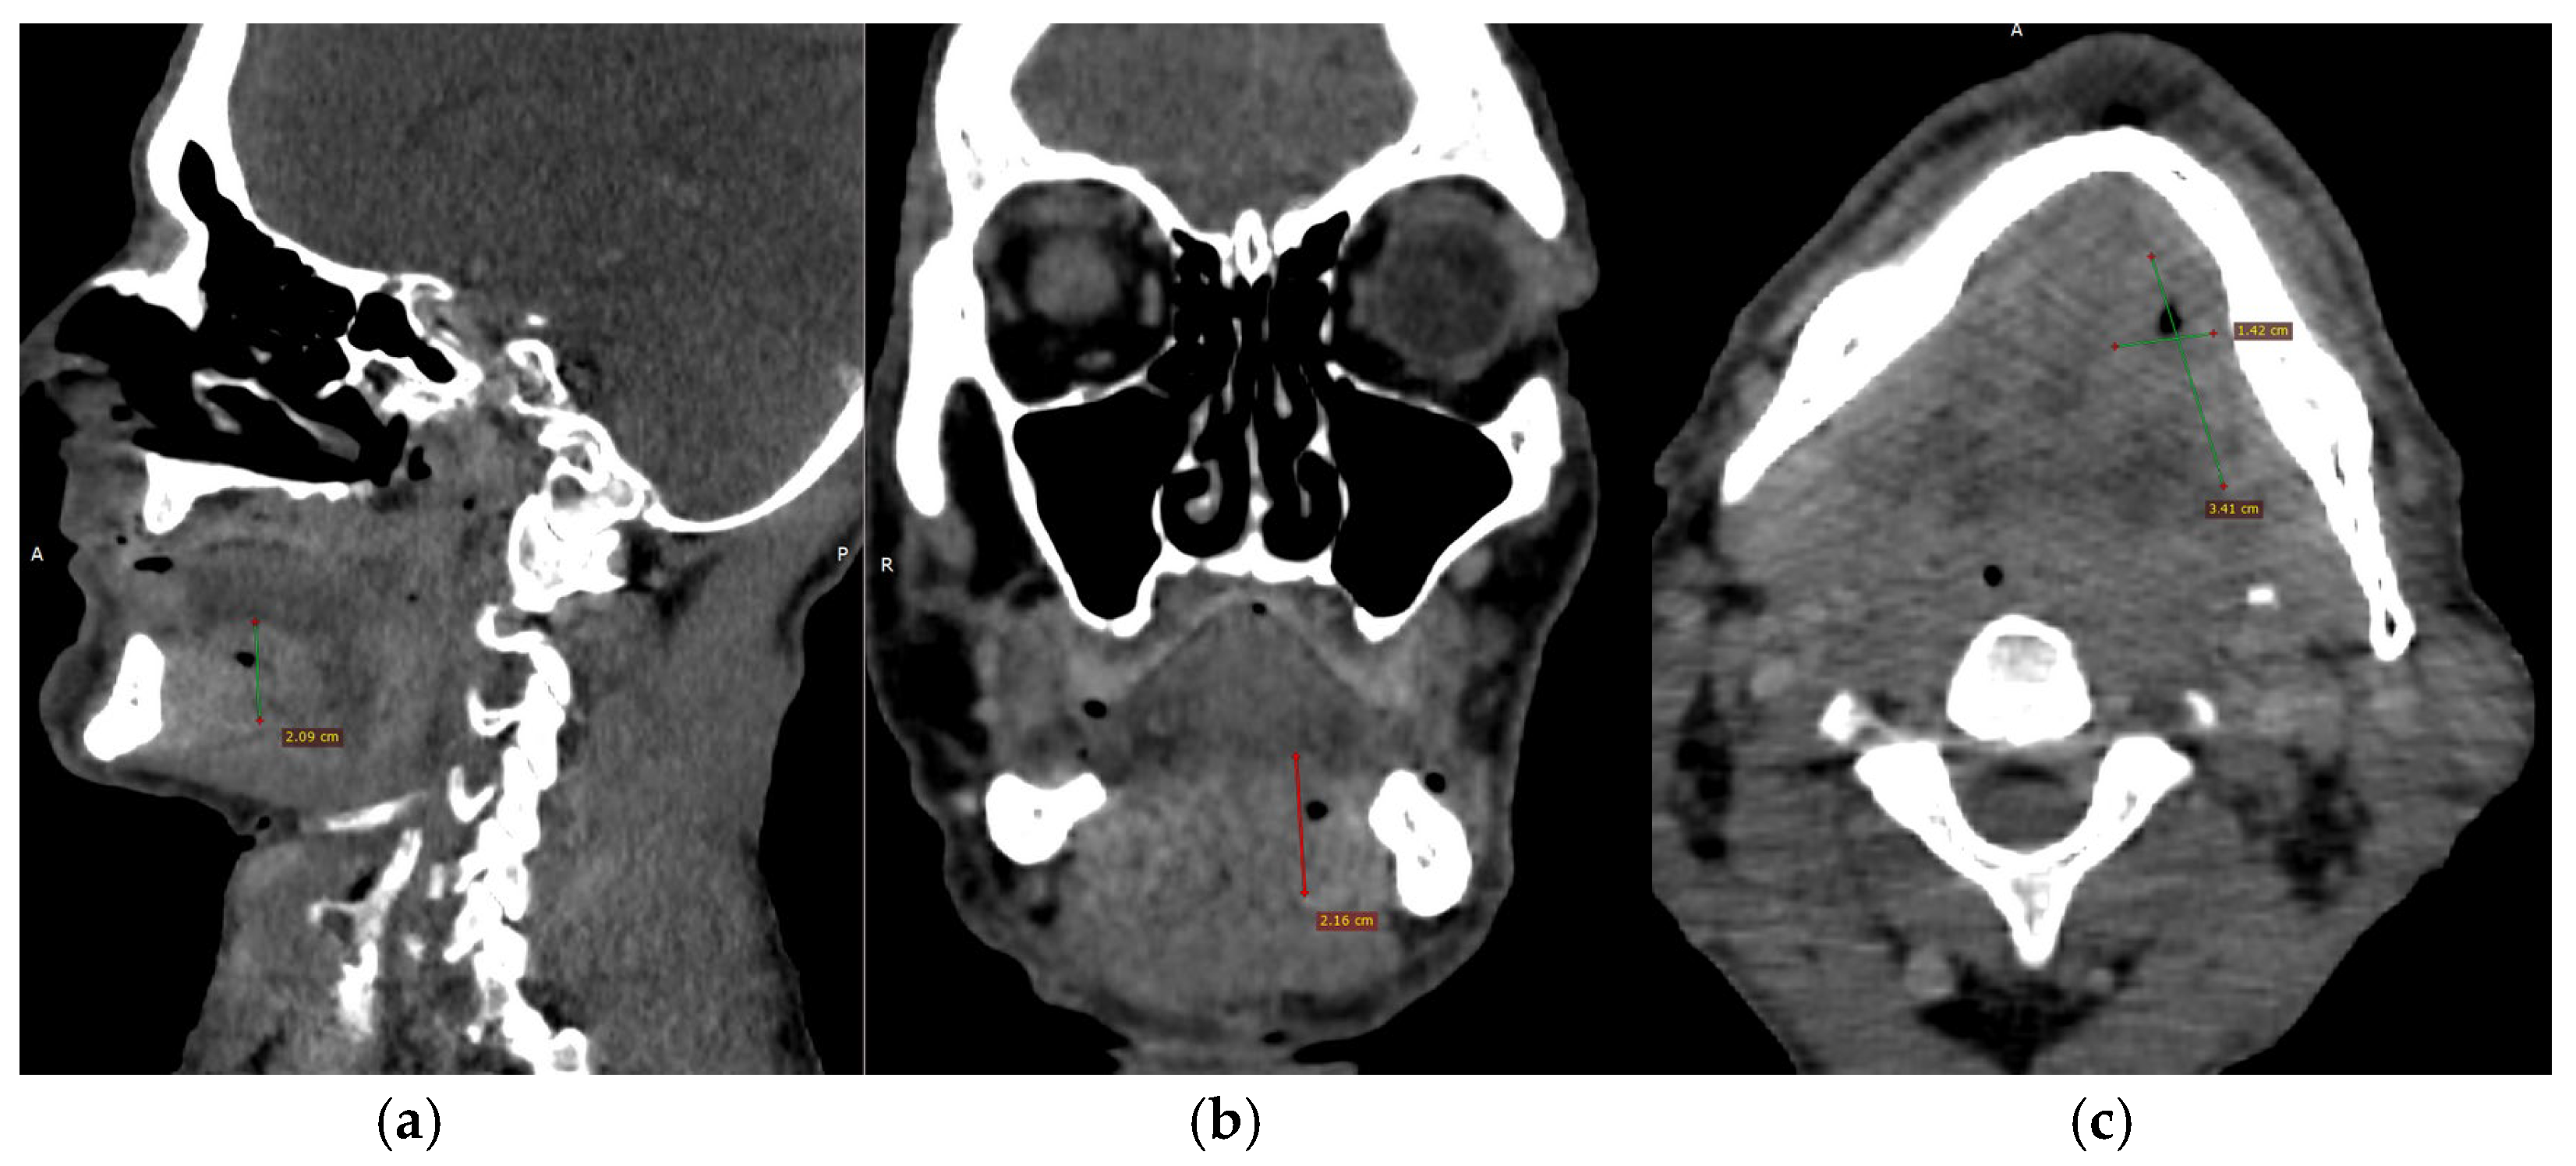

CECT of the oral and submandibular region revealed a heterodense lesion within the left sublingual space, measuring approximately 34 × 13 × 20 mm, with a depth of 18 mm (Figure 3). The lesion exhibited fluid content with small central air inclusions and peripheral contrast enhancement, without evidence of adjacent osseous destruction (Figure 4).

Figure 3.

(a–c) CECT images (a) Axial section showing a heterodense lesion in the left sublingual space with central necrosis and peripheral enhancement. (b) Coronal section demonstrating the lesion confined to the left side without crossing the midline. (c) Sagittal section illustrating the depth of infiltration (18 mm) without evidence of mandibular bone involvement.

Figure 4.

Three-dimensional CT reconstruction in left lateral view demonstrating the craniofacial skeleton, cervical vertebrae, and upper thoracic cage with no bone destruction.

It remained confined to the left side, without crossing the midline. The radiologic appearance was suggestive of a necrotic neoplasm or, less likely, an infectious etiology. Additional findings included a few punctate calcifications within the left parotid gland and an associated 4 mm hypodense area. A well-circumscribed, cystic-appearing lesion measuring 15 mm was also noted in the left subclavicular region, radiologically consistent with a possible lymphangioma. The carotid-jugular vascular axis was patent bilaterally with preserved caliber, although parietal calcifications were observed at the carotid bifurcations on both sides.